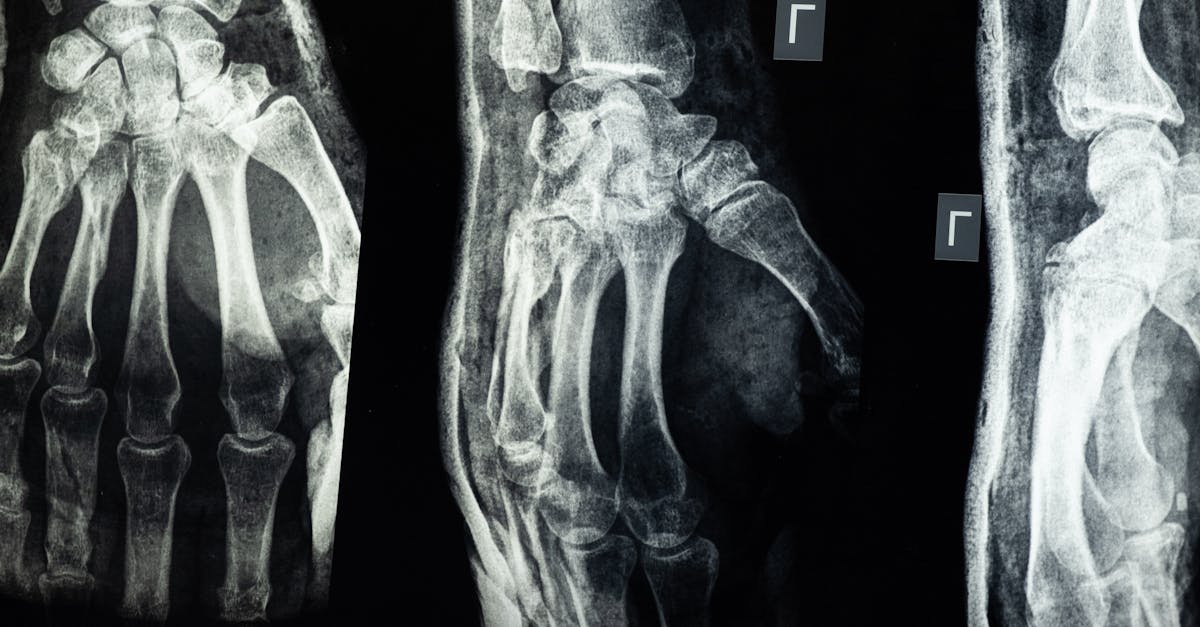

Fluoroscopy imaging is a diagnostic technique that utilizes continuous X-ray beams to capture real-time images of the body in motion. This dynamic imaging method allows healthcare providers to observe structures like the gastrointestinal tract, blood vessels, and joints as they function and move within the body. By providing live feedback, fluoroscopy aids in guiding certain medical procedures and interventions with precision and accuracy.

Common uses of fluoroscopy imaging include assessing swallowing function, detecting blockages or abnormalities in the digestive system, guiding the placement of catheters or feeding tubes, and assisting in certain types of surgeries. Its ability to capture moving images in real time makes it a valuable tool for diagnosing conditions that may not be visible on static X-ray images. Despite its advantages in providing immediate visual feedback, fluoroscopy does expose patients to some radiation, so healthcare providers carefully weigh the benefits against the risks when recommending this imaging technique.

Fluoroscopy imaging is a widely utilized medical technique that involves real-time X-ray imaging to capture moving internal structures of the body. One of the common uses of fluoroscopy imaging is in the field of orthopedics for guided interventions such as setting fractures, joint injections, or spinal procedures. Physicians can accurately visualize the placement of needles, screws, or other medical devices in the body, ensuring precision and reducing the risk of complications during these procedures.